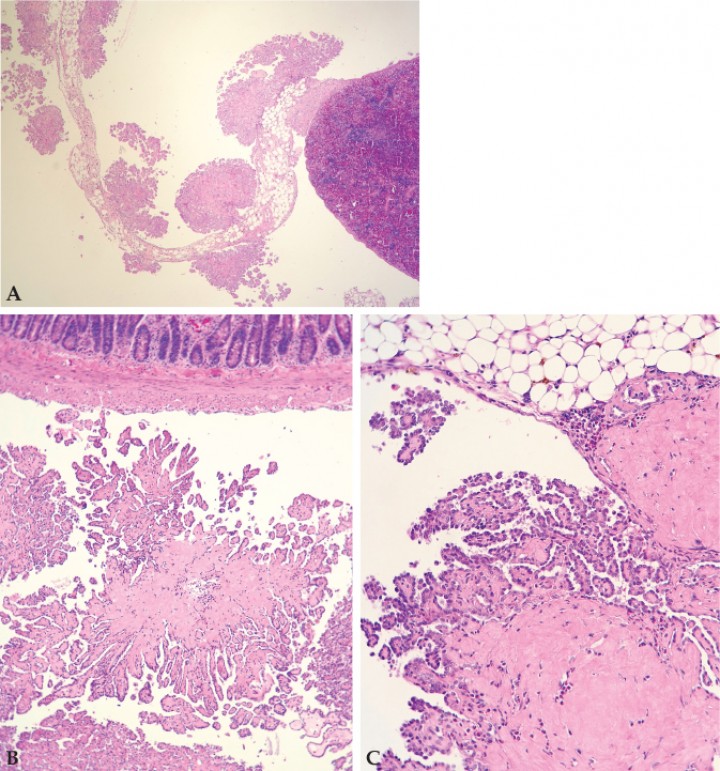

Se procedió a la preparación de las muestras en bloques de parafina y tinción con hematoxilina-eosina. Los resultados del estudio histopatológico revelaron un mesotelioma en el peritoneo visceral. Las células neoplásicas mesoteliales se organizaban en crecimientos papilares en el peritoneo visceral de diversos órganos y omento/tejido adiposo mesentérico, los cuales se apoyaban en una cantidad generalmente baja de estroma. Las células mesoteliales se caracterizaban por un núcleo de redondo a elíptico con la cromatina laxa y 0-2 nucléolos muy pequeños, así como por la presencia de escaso citoplasma. La anisocitosis y anisocariosis eran moderadas, mientras que el pleomorfismo y la anaplasia eran de grado bajo. El índice mitótico era muy bajo (0-1 mitosis por campo de 40 aumentos). En algunos focos, el estroma estaba expandido por depósitos de material eosinófilo amorfo, interpretado como probable amiloide intratumoral, así como por infiltrados de granulocitos y mastocitos, y depósitos de hemosiderina. También se encontraron otras lesiones como depósitos intracitoplasmáticos de pigmento marrón verde en el riñón, hematopoyesis extramedular moderada y hemosiderosis leve de macrófagos en el bazo, pero sin relación evidente con la presentación clínica (Fig. 5).

<p>(<strong>A</strong>) Crecimientos papilares de células mesoteliales neoplásicas en el peritoneo visceral del bazo (Hematoxilina-eosina, x5,76). (<strong>B</strong>) Intestino (Hematoxilina-eosina, x14,4). (<strong>C</strong>) Mesotelioma con formaciones papilares adherido a tejido adiposo y mesenterio con material eosinófilo intratumoral compatible con amiloide (Hematoxilina-eosina, x28,8).</p>

(A) Crecimientos papilares de células mesoteliales neoplásicas en el peritoneo visceral del bazo (Hematoxilina-eosina, x5,76). (B) Intestino (Hematoxilina-eosina, x14,4). (C) Mesotelioma con formaciones papilares adherido a tejido adiposo y mesenterio con material eosinófilo intratumoral compatible con amiloide (Hematoxilina-eosina, x28,8).